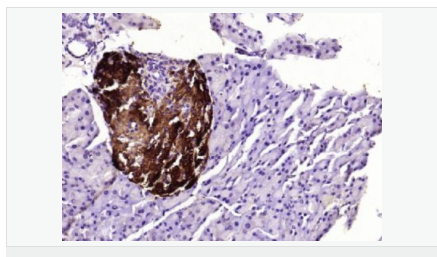

| 產(chǎn)品應(yīng)用 | WB=1:500-2000 ELISA=1:5000-10000 IHC-P=1:100-500 IHC-F=1:100-500 ICC=1:100-500 IF=1:100-500 (石蠟切片需做抗原修復(fù)) not yet tested in other applications. optimal dilutions/concentrations should be determined by the end user. |

| 產(chǎn)品介紹 | This gene encodes an aldo-keto reductase that catalyzes the NADPH-dependent reduction of pteridine derivatives and is important in the biosynthesis of tetrahydrobiopterin (BH4). Mutations in this gene result in DOPA-responsive dystonia due to sepiaterin reductase deficiency. A pseudogene has been identified on chromosome 1. [provided by RefSeq, Jul 2008] Function: Catalyzes the final one or two reductions in tetra-hydrobiopterin biosynthesis to form 5,6,7,8-tetrahydrobiopterin. Subunit: Homodimer. Subcellular Location: Cytoplasm. Post-translational modifications: In vitro phosphorylation of Ser-213 by CaMK2 does not change kinetic parameters. DISEASE: Defects in SPR are the cause of dystonia DOPA-responsive due to sepiapterin reductase deficiency (DRDSPRD) [MIM:612716]. In the majority of cases, patients manifest progressive psychomotor retardation, dystonia and spasticity. Cognitive anomalies are also often present. The disease is due to severe dopamine and serotonin deficiencies in the central nervous system caused by a defect in BH4 synthesis. Dystonia is defined by the presence of sustained involuntary muscle contractions, often leading to abnormal postures. Similarity: Belongs to the sepiapterin reductase family. SWISS: P35270 Gene ID: 6697 Database links: Entrez Gene: 6697 Human Omim: 182125 Human SwissProt: P35270 Human Unigene: 301540 Human Important Note: This product as supplied is intended for research use only, not for use in human, therapeutic or diagnostic applications. |